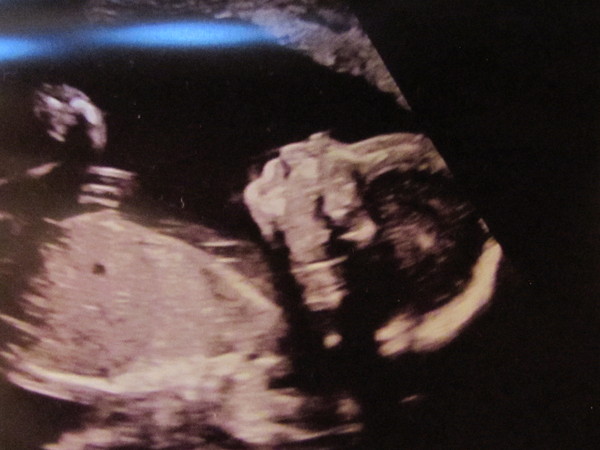

dreamofhungarianlanterns · 17/12/2016 09:02

On the other hand... look at this little face!!!

20 week scan yesterday, all looks well and confirmed he's a boy (as far as they will). Feeling rather giddy Smile

Glad yours went well savage

That is a great picture dream !